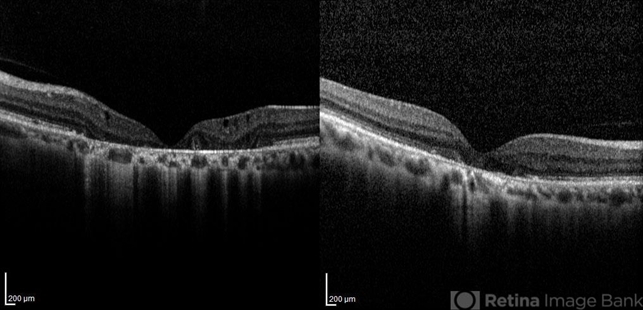

- optical coherence tomography (OCT), central areolar choroidal dystrophy (CACD)

- OCT images of both eyes of a 58-year-old man with progressive loss of vision. VA OD is 20/60 and VA OS is 20/400.